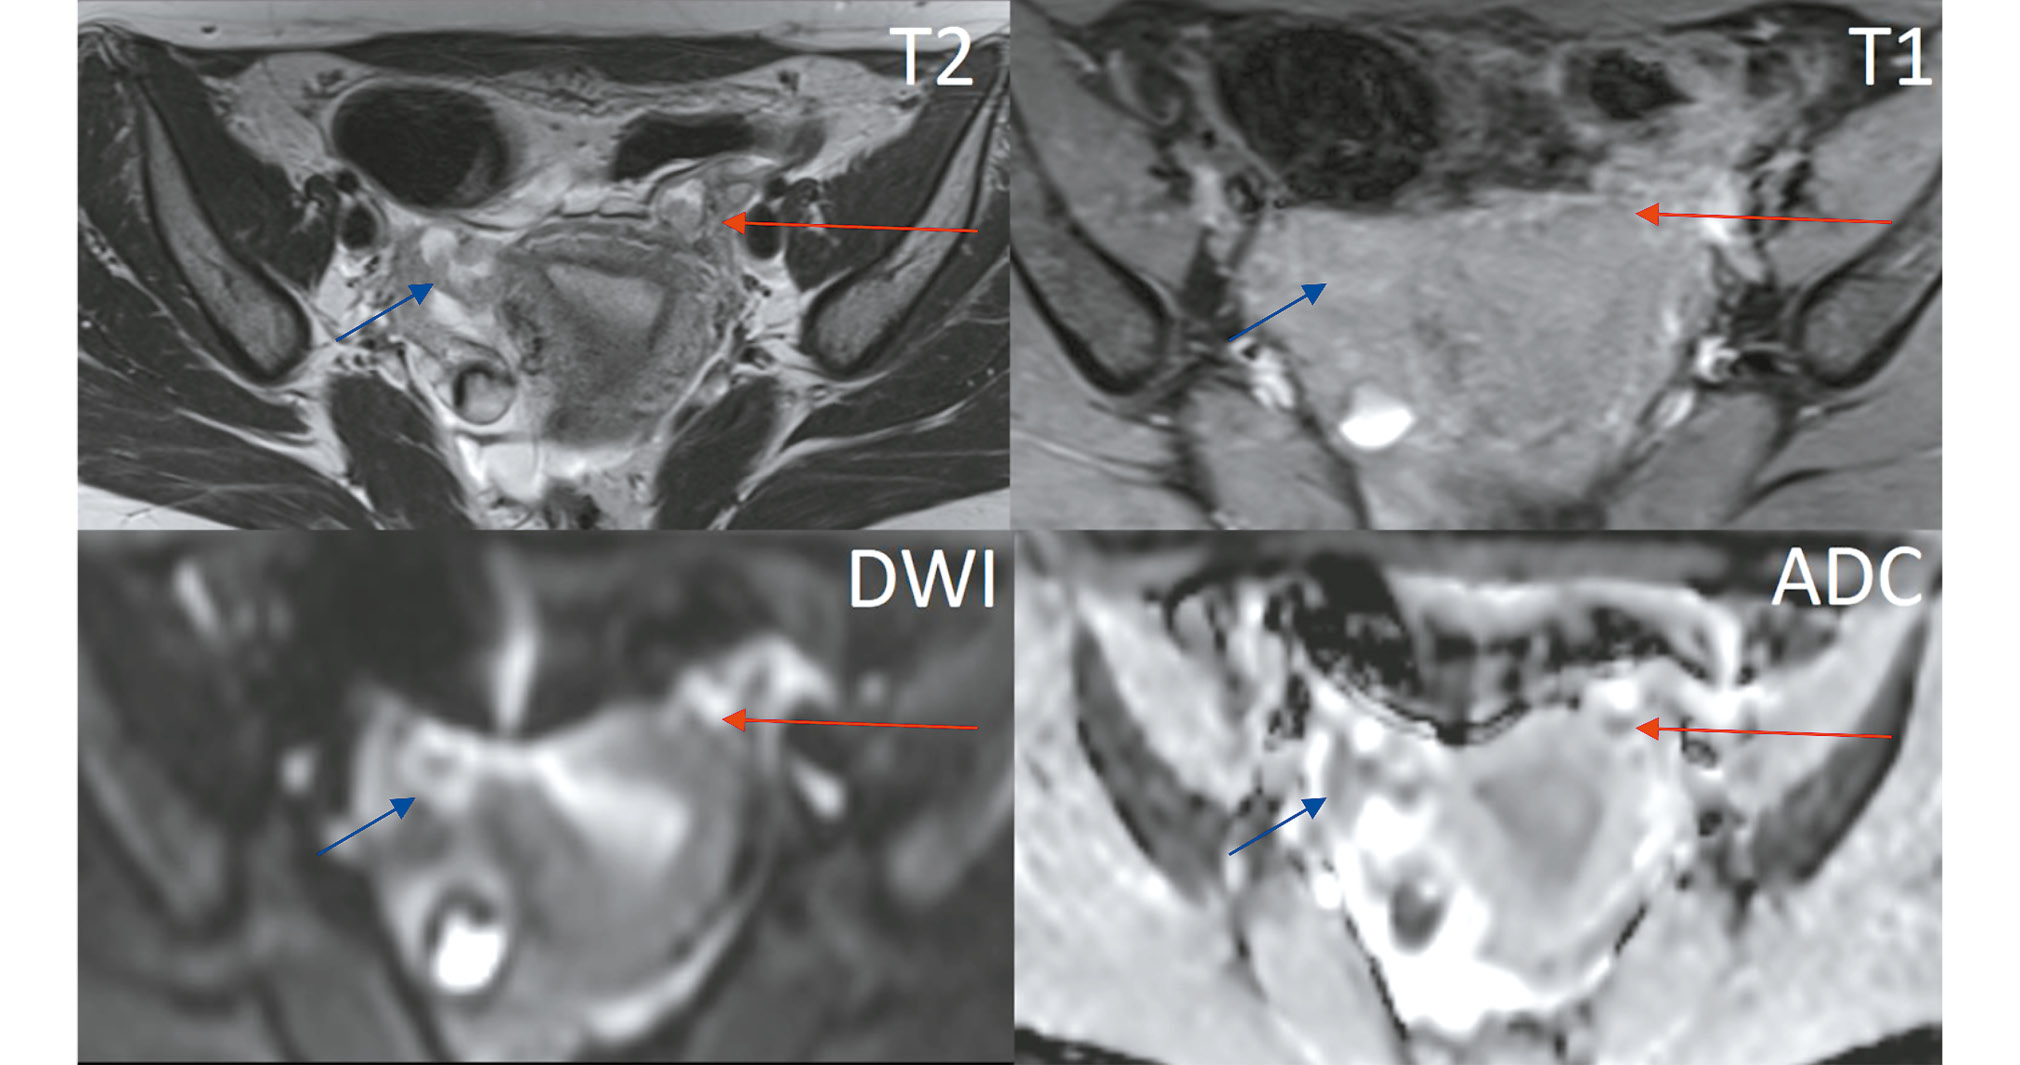

A tubular structure with high fluid signal intensity and an irregular lumen, measuring up to 17 mm, was located adjacent to the anterior and outer contours of the right ovary. This structure had multiple hypervascular solid nodules on the walls and showed signs of restricted diffusion in the DWI sequence (Fig. 4). A smaller structure with similar MRI characteristics was observed on the left (Fig. 5).

Fig. 5. Pelvic magnetic resonance imaging (axial view). Similar solid nodules are present in the left fallopian tube (red arrow). The right fallopian tube appears convoluted in this slice (blue arrow).

- Oblong or tubular lesions in the adnexal area, often with relatively uniform fluid signal intensity (low on T1WI and high on T2WI). In our case, the lesion contained several solid foci on the walls, clearly visible against the backdrop of the distended fallopian tube. These solid foci showed restricted diffusion on DWI/ADC and early contrast uptake in the dynamic contrast-enhanced sequence.

- Fluid in the fallopian tubes (hydrosalpinx): This condition results from tumor secretions that block the fallopian tube, causing colic-like pelvic pain due to stretching. The contents of the hydrosalpinx can vary, leading to different MRI signals. In our case, the fallopian tubes were distended with serous fluid, although a hemorrhagic component due to recurrent bleeding is also possible.